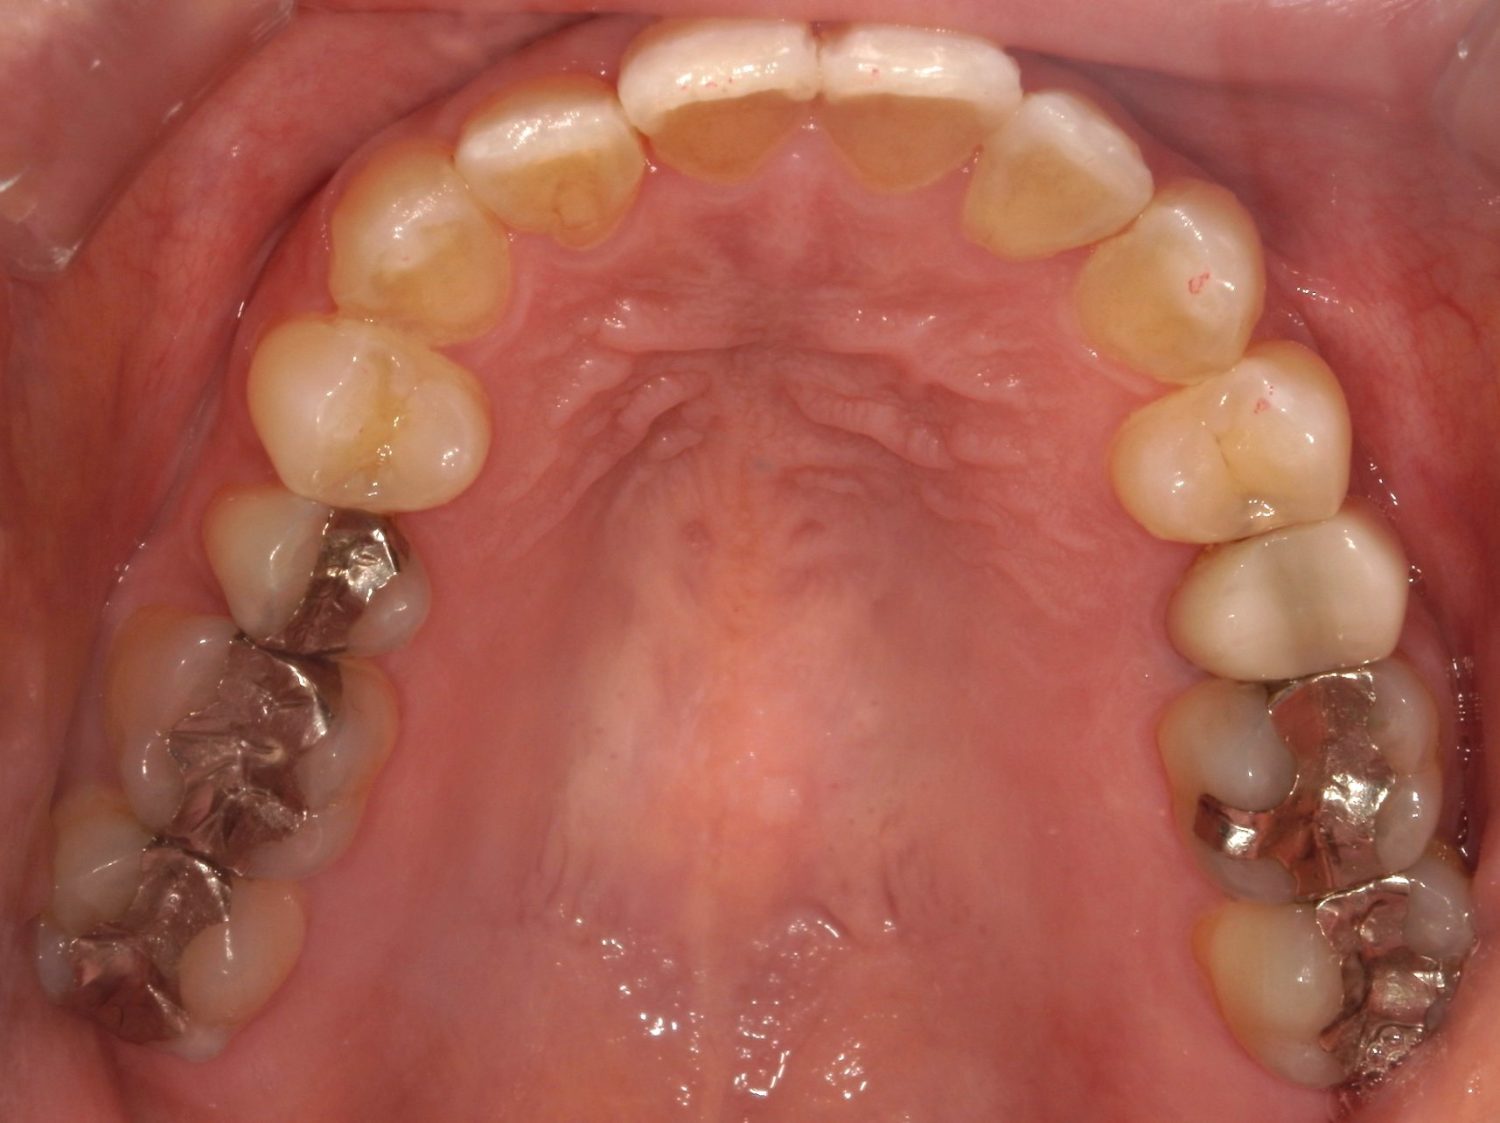

Before

After

主訴

上の前歯の横の歯が後ろに引っ込んでいるのでセラミックの被せ物で治したい。

治療内容

ワイヤー矯正で治しました。

治療費

115,500円(税込)(リテーナー込み)

治療期間

4か月

通院回数

5回

想定されたリスク

※当該部位の上下のかみ合わせが反対になっていましたので、上の歯を前に動かすときに引っかかって動かない可能性がありました。

石毛 俊作先生

大神宮デンタルクリニック

セラミックの被せ物で治すと健全な歯を削ることになってしまうので、患者様と相談し、矯正治療で治すことにしました。